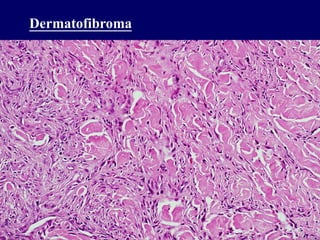

Dermatofibroma

Benign fibrous histiocytoma

Usually in skin

Mixture of fibroblasts,

myofibroblasts, histiocytes

Surgical excision

Dermatofibroma Benign fibrous histiocytoma Usuallyin skin Mixture of fibroblasts, myofibroblasts, histiocytes Surgical excision